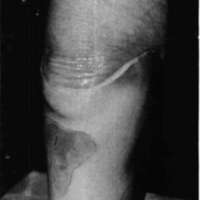

When the socket is filled with plaster, a positive model that has been redefined by the alginate under weight-bearing conditions is obtained. When the plaster has set, the test socket is removed by cutting it off. The alginate will adhere to the cured plaster model (Fig. 6).

Figure 6. Alginate is removed from new positive model before smoothing and vacuum-forming definitive socket or a new check socket.The new positive model is now evaluated. Information such as location and thickness of the alginate fill is useful feedback concerning the original casting and model modification. At this point the alginate is removed and the new positive model is smoothed using sand screen. The model is now ready either for use as a follow-up transparent test socket or for fabricating a definitive socket.